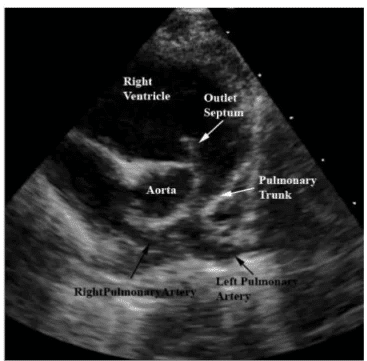

Transposição das grandes artérias

Visualização alterada da saída dos vasos principais requer avaliação em cortes de três vasos e três vasos-traqueia.

Tetralogia de Fallot

Conjunto de quatro alterações anatômicas, incluindo estenose pulmonar e aorta sobre o septo.

A imagem ecográfica a seguir representa a anatomia cardíaca observada na tetralogia de Fallot, destacando a presença de uma obstrução na via de saída do ventrículo direito (estenose pulmonar) associada a um defeito no septo interventricular.